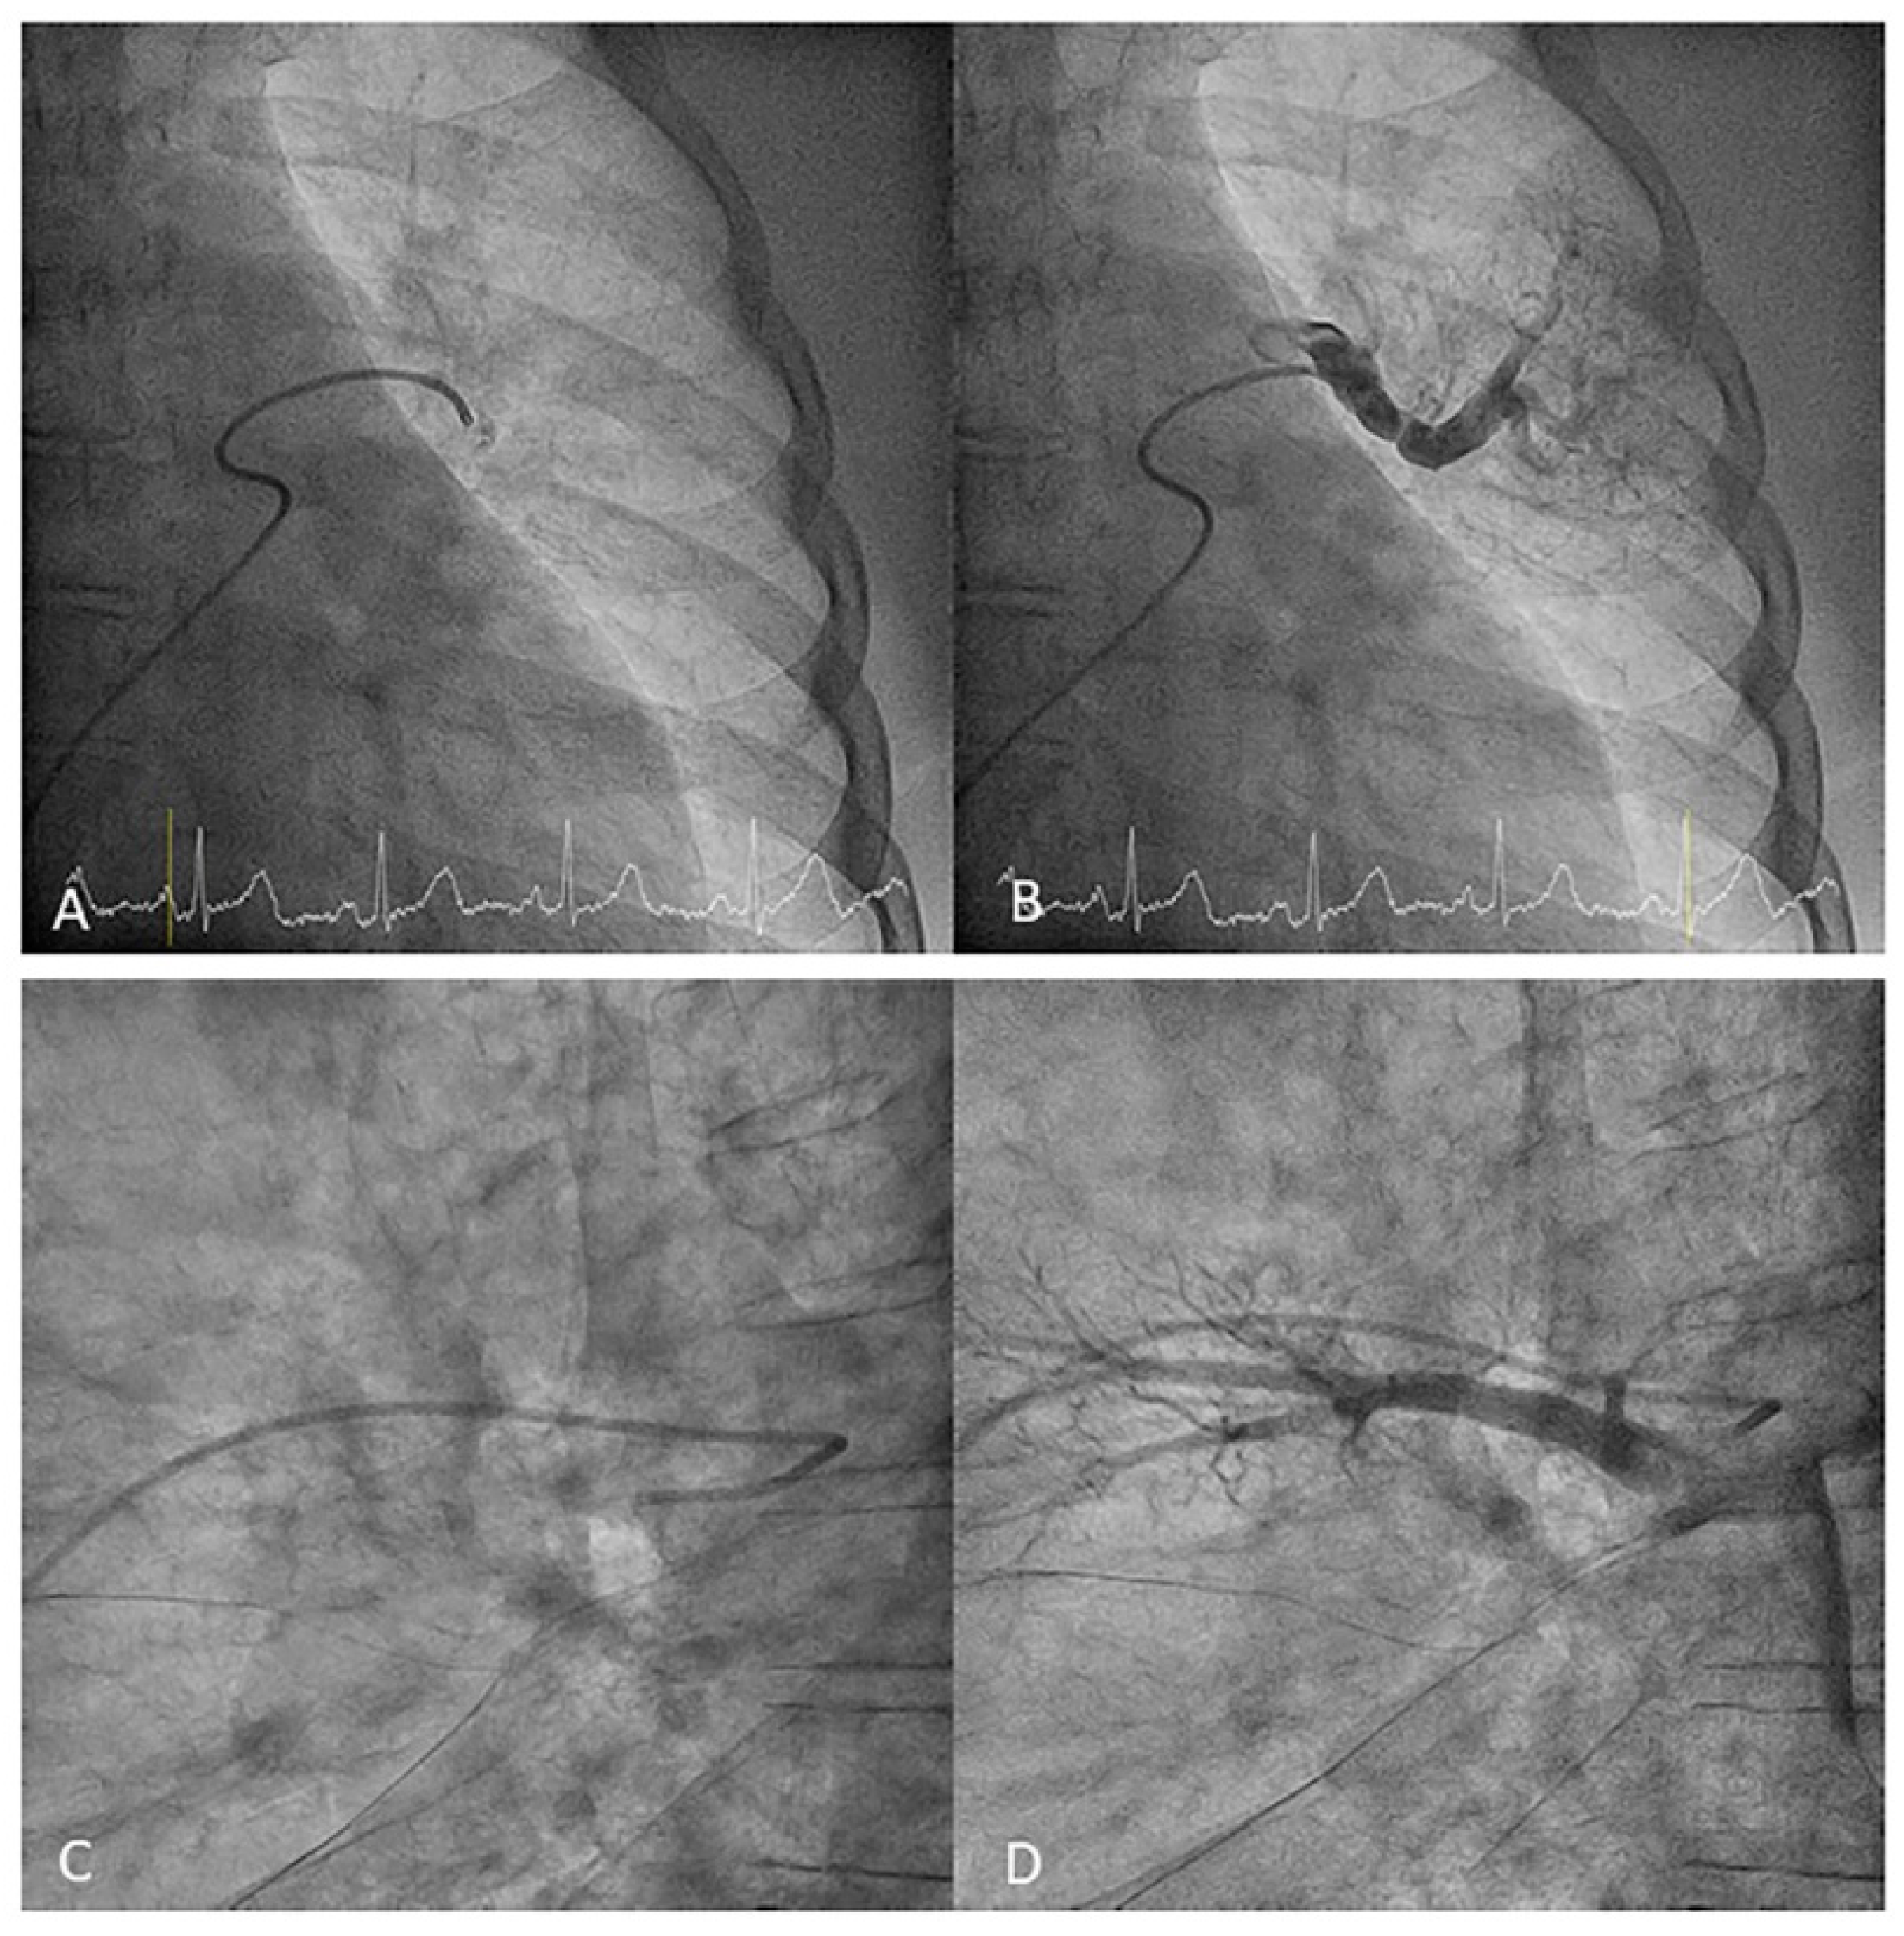

- Lingula. The lingula artery is easily cannulated in the AP view with the JL 3.5/4 catheter (depending on the PA dilatation). The maneuver and position in the AP view is the same as described for the anterior segmental artery of the left upper lobe (A3), though somewhat lower (Figure 25). Amplatz left 1 or 2 is also a good choice for catheterization of the lingula branches. In addition, this catheter gives extra support when performing BPA of these branches. The two lingula segmental arteries are well displayed in the lateral and in the cranial RAO/cranial AP views.